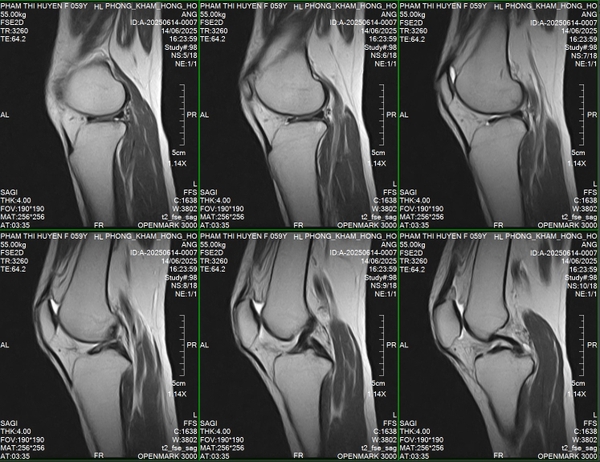

🌿Mới đây, Phòng khám đa khoa Hồng Hoàng đã lắp đặt xong hệ thống chụp cộng hưởng từ OPENMARK III – 0.3 Tesla, sau đó tiếp tục được đào tạo và chuyển giao công nghệ từ sự hỗ trợ của các kỹ thuật viên trong nước và nước ngoài.

🐟𝐌𝐑𝐈 𝟎.𝟑𝐓 𝐎𝐏𝐄𝐍𝐌𝐀𝐑𝐊 𝐈𝐈𝐈 – là hệ thống từ trường thấp, nhưng với thiết kế tối ưu, có chất lượng cao và phần mềm xử lý hình ảnh thông minh, hoàn toàn có khả năng chẩn đoán chính xác các nhóm bệnh lý sau:

🔹𝐂𝐨̛ 𝐱𝐮̛𝐨̛𝐧𝐠 𝐤𝐡𝐨̛́𝐩: phát hiện rách gân cơ, viêm khớp, tổn thương sụn – dây chằng – thoái hóa khớp.

🔶Hình ảnh đầu ra rõ nét, hỗ trợ bác sĩ đưa ra quyết định lâm sàng nhanh chóng và chính xác.